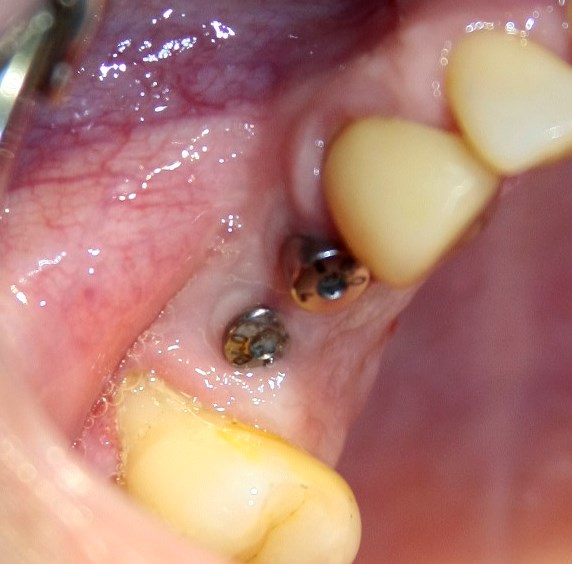

Опыт применения коллагеновой матрицы Mucograft в клинической практике.